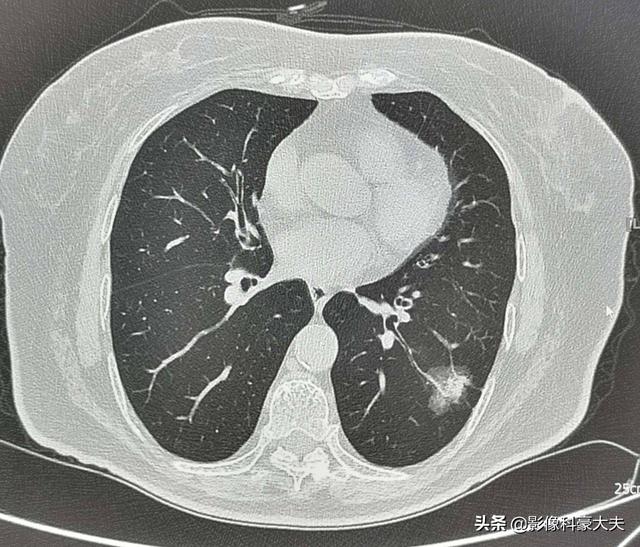

Par exemple, cette femme d'âge moyen présentant un nodule de verre à membrane mixte de 2,2 cm dans le poumon inférieur gauche est un nodule à haut risque, qui présente en fait les signes classiques d'un adénocarcinome pulmonaire, à savoirOmbre en verre dépoli bien définie avec entrée et épaississement vasculaire, signe d'insufflation bronchique, atteinte pleurale distale, pathologie chirurgicale de l'adénocarcinome pulmonaire invasif.Ce type de lésion n'est pas recommandé pour le suivi et doit faire l'objet d'un examen plus approfondi afin d'éviter les métastases et les retards de traitement.

Si les nodules sont malins, ils ont généralement une forme irrégulière, lobulée (les cellules tumorales se développent de manière irrégulière dans toutes les directions), et peuvent être vus comme un signe vacuolaire, un signe de bavure marginale, un signe de vaisseaux sanguins alimentant la tumeur, un signe de dépression pleurale adjacente, et une augmentation de la taille des nodules en verre dépoli ou des composants solides lors de l'examen de suivi, etc.

En général, les nodules d'un diamètre supérieur à 8 mm doivent faire l'objet d'une attention particulière, surtout s'ils sont de forme irrégulière, voire accompagnés d'un motif en forme de bavure, ou mélangés avec le réel et l'imaginaire, adjacents à la plèvre et apparaissant comme une dépression pleurale, nous devons être très attentifs à la possibilité d'une tumeur maligne. Si nécessaire, il faut procéder à une ponction-biopsie ou à une excision directe.